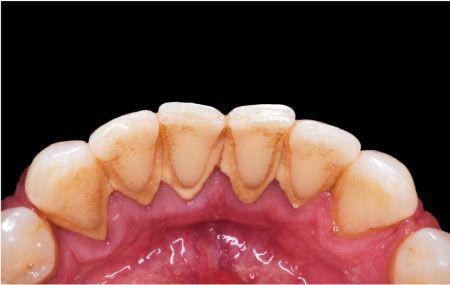

Causa de la periodontitis

Si no tiene una buena higiene la placa y el sarro se acumulan en la base del diente, esto hace que la encia se inflame y esta misma se distancie de la superficie dentaria dando paso a una bolsa periodontal. Estas se llenan de bacterias provocando infecciones, si estas continuan con el tiempo, al final destruyen los tejidos y el hueso al rededor del mismo, asi perdemos estabilidad y sustencion de nuestro diente.

Ademas de poca higiene, la placa bacteriana, tambien existe otros factores locales y sistematicas que modifican la respuesta del huesped ante la irritacion bacteriana, como el tabaquismo, diabetes, disposicion genetica.

Sintomas

Mal aliento constante

Encias rojas o inflamadas

Dolor, sangrado en las encias